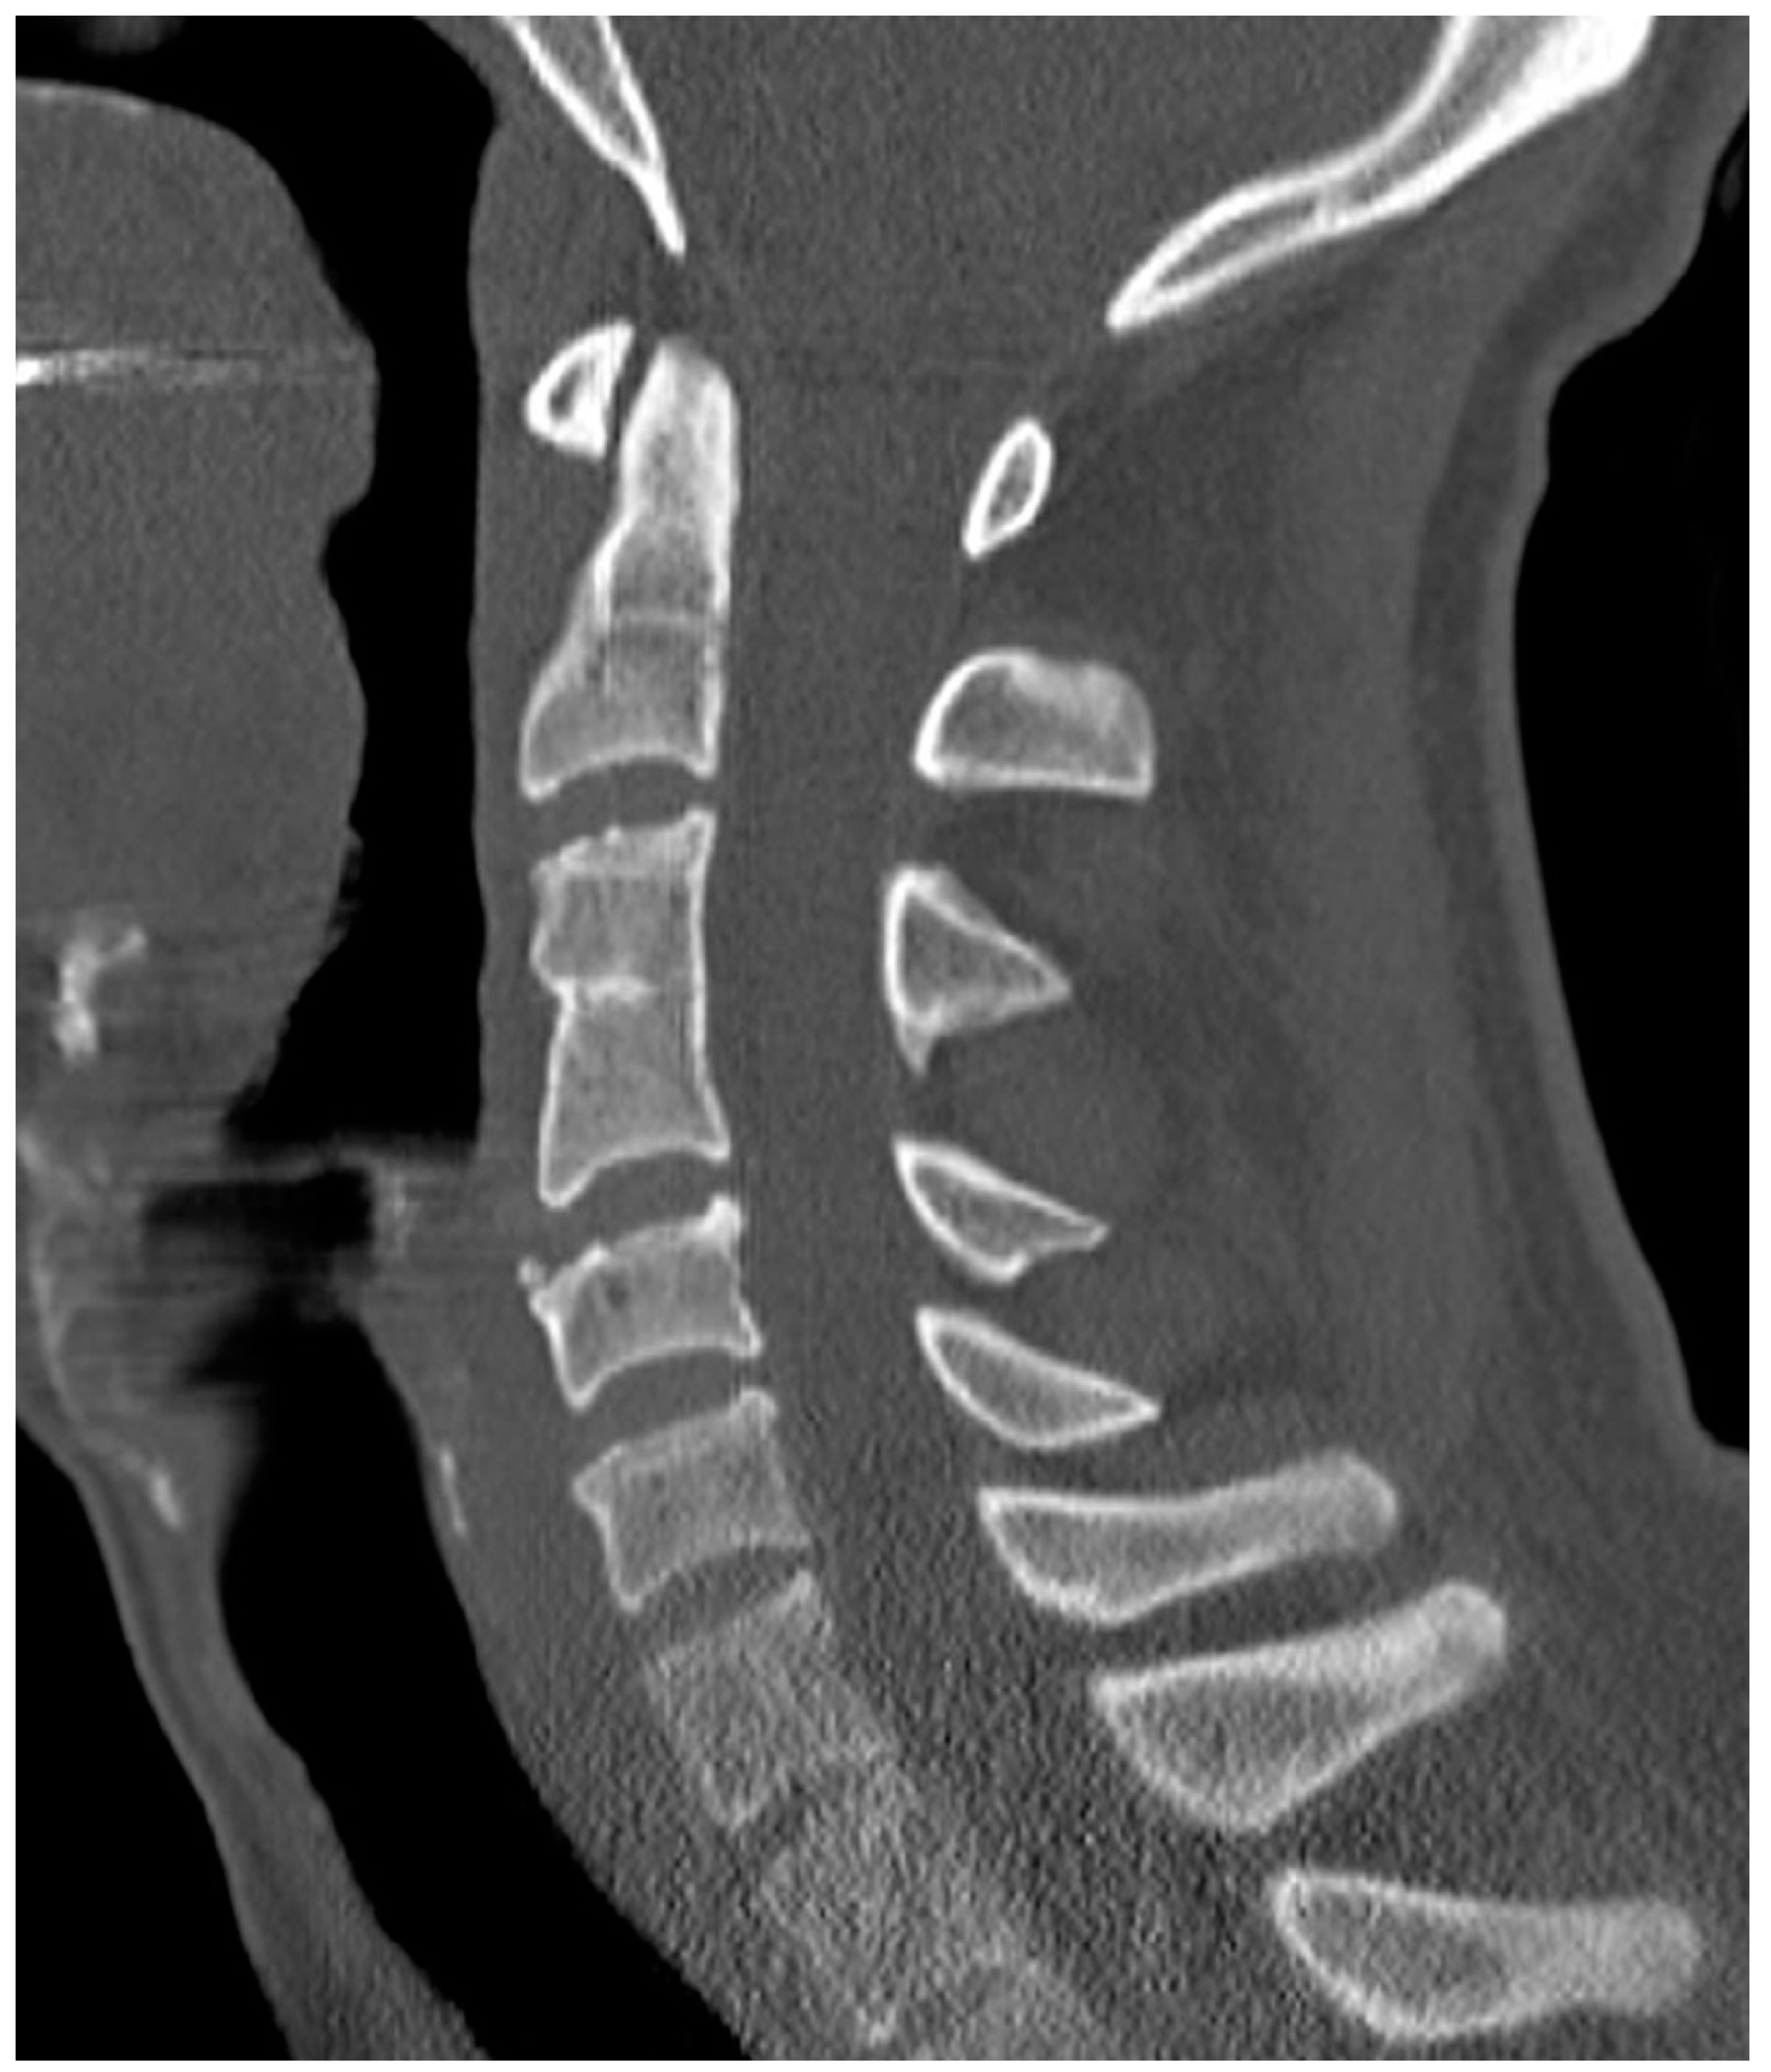

Are Congenital Cervical Block Vertebrae a Risk Factor for Adjacent Segment Disease? A Retrospective Cross-Sectional CT and MR Imaging Study